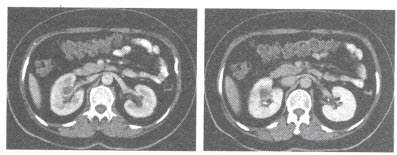

E.CT对肾癌诊断和分期的准确率超过90%

157、多项选择题

男,65岁,左侧腰背部胀痛伴无痛性全程血尿3月余,CT平扫及增强检查如图所示,下列说法正确的是()

A.平扫时见左肾上极有一软组织肿块影,其边界较清楚

B.增强扫描肾皮质期可见肿块明显强化,其内亦有无强化区

C.增强扫描肾实质期可见肿块强化迅速下降,但密度比平扫时仍要高

D.考虑为左侧肾癌

E.考虑为左侧肾错构瘤